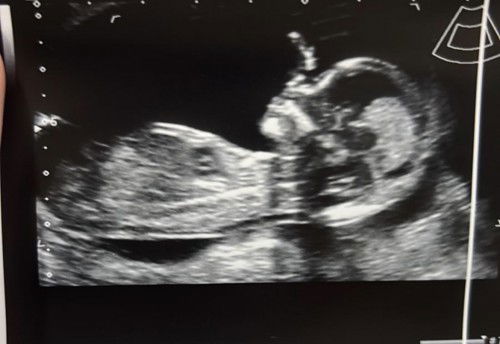

Is my ultrasound scan normal? Saw someone posting about only finding out her baby has down syndrome during birth as the doctor did not detect it before. She said she looked back at her ultrasound and realised her baby has short/no nasal bone. My hubs assured me saying that the baby has not developed features yet. Should i see a the baby’s nose in my FTS? Btw i only did FTS and everything was low risk so i did not do NIPT. Now im abit worried